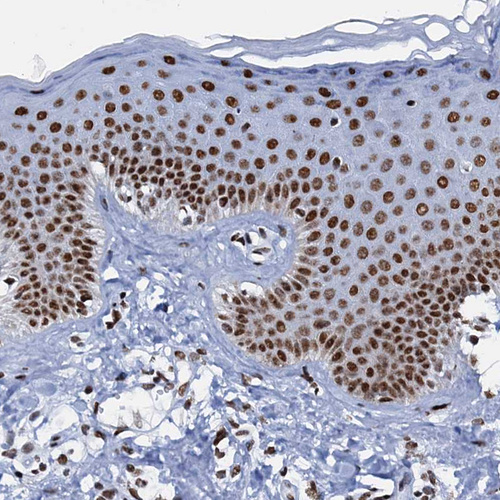

Immunohistochemical staining of human cerebral cortex, gastrointestinal, squamous epithelia and testis using Anti-SLTM antibody HPA040256 (A) shows similar protein distribution across tissues to independent antibody HPA040381 (B).